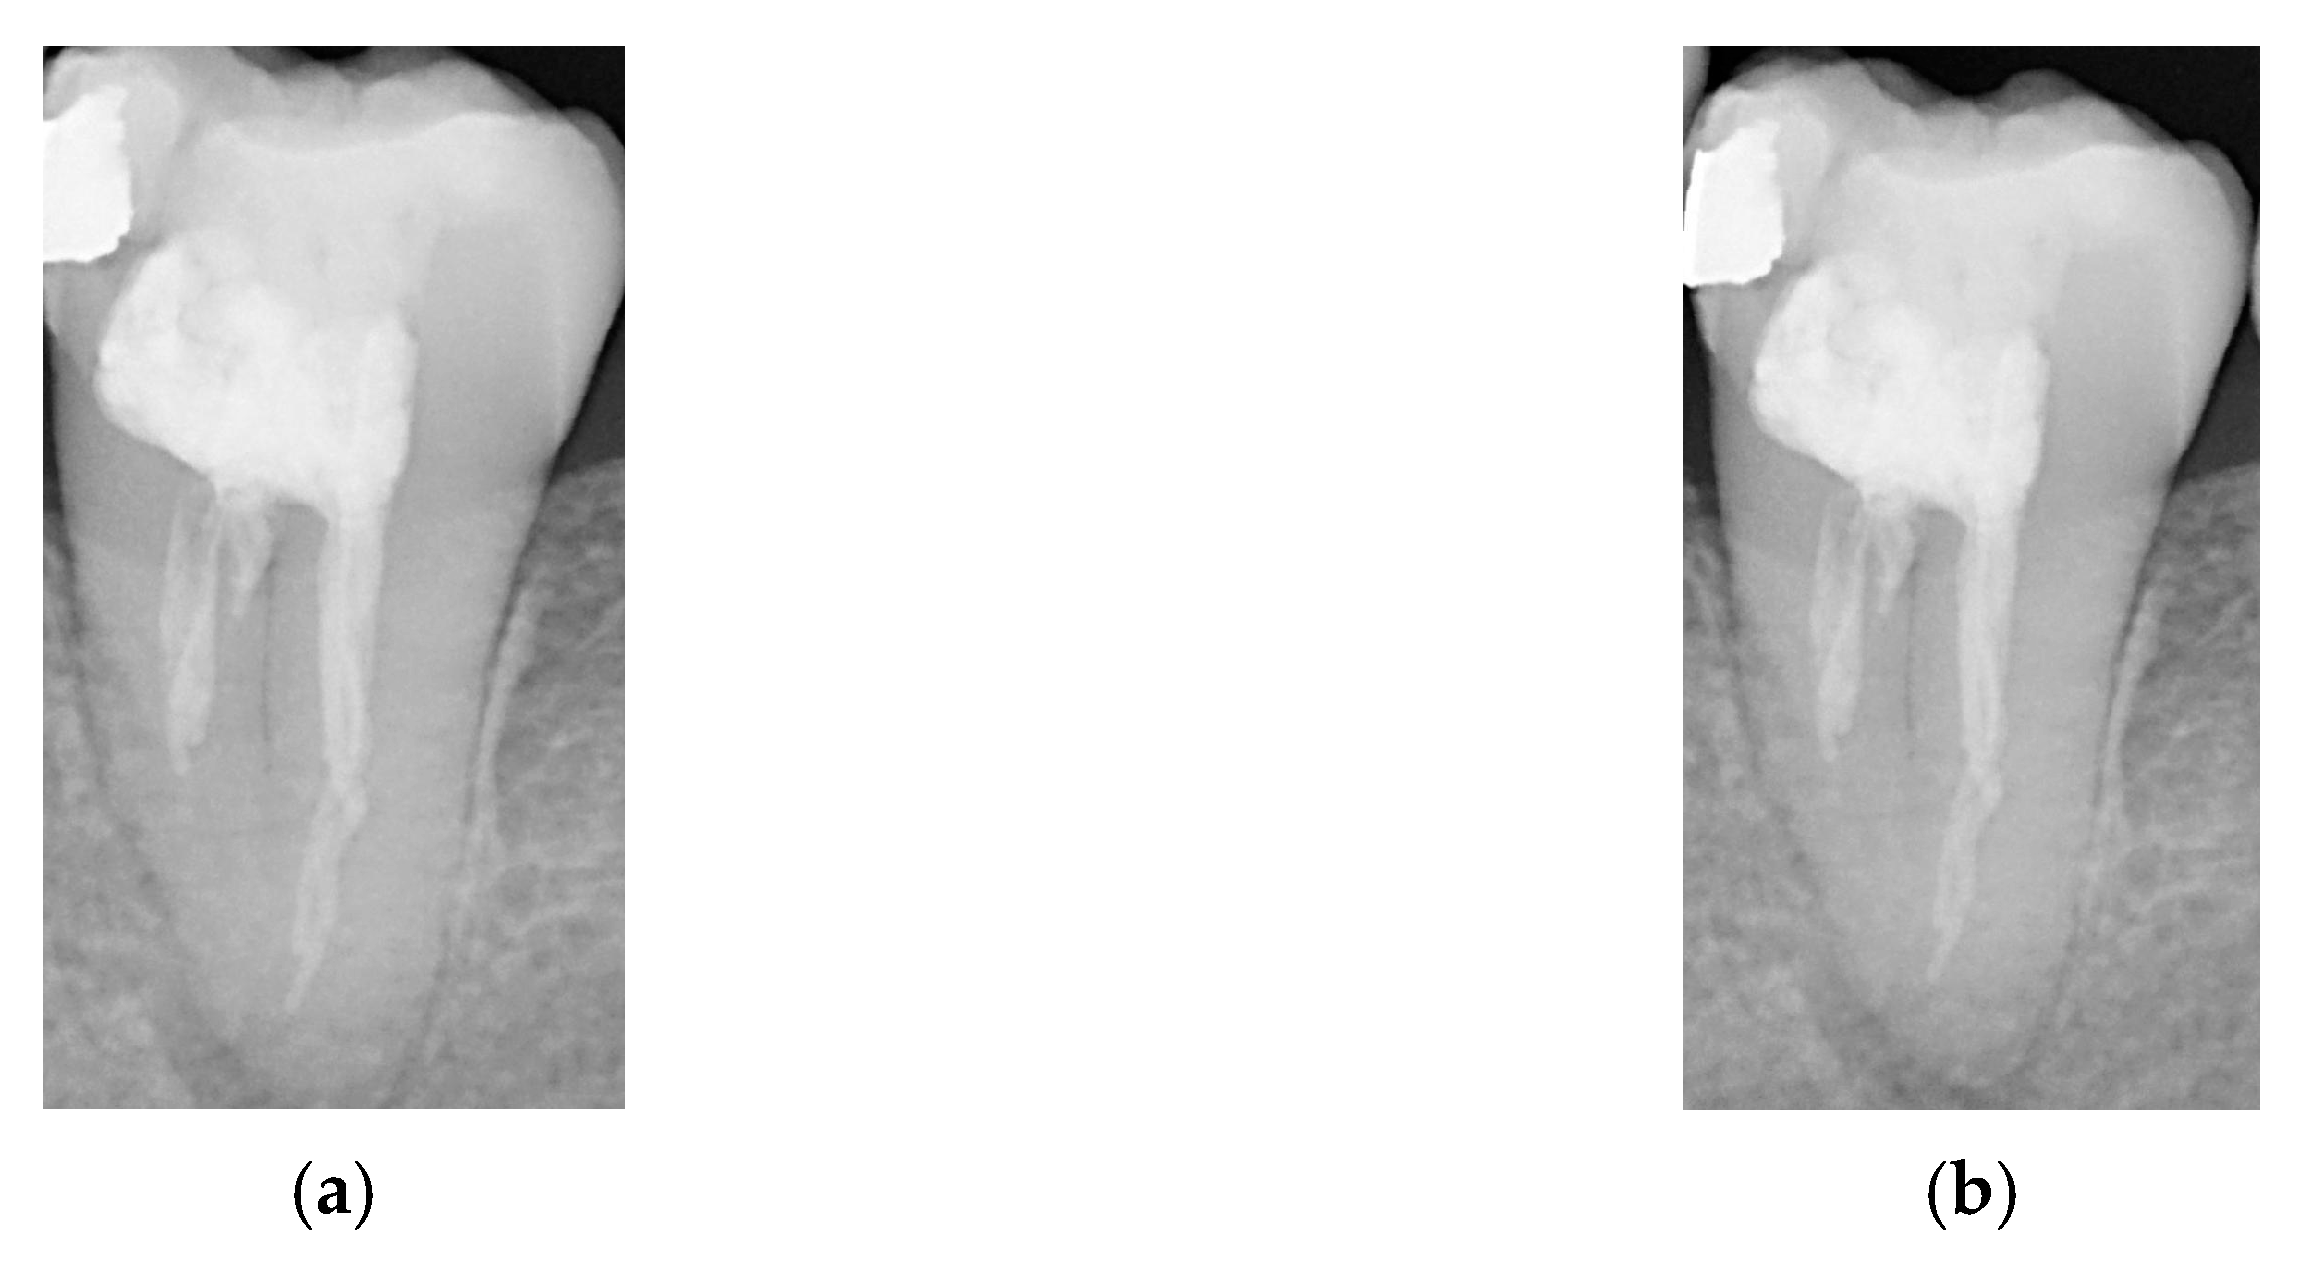

- Aspect 4: Image Enhancement